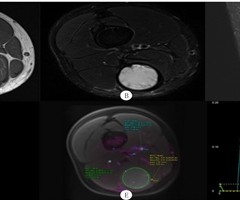

磁共振成像对四肢软组织血肿的诊断价值

[摘要]目的探讨磁共振成像(MRI)对四肢软组织血肿的诊断价值。方法结合文献回顾性分析14例四肢软组织血肿病人的MRI表现和临床资料。结果14例病人中,男9例,女5例,年龄 11~80 岁。病变部位和分布:肌内血肿11例,皮下血肿3例;下肢...